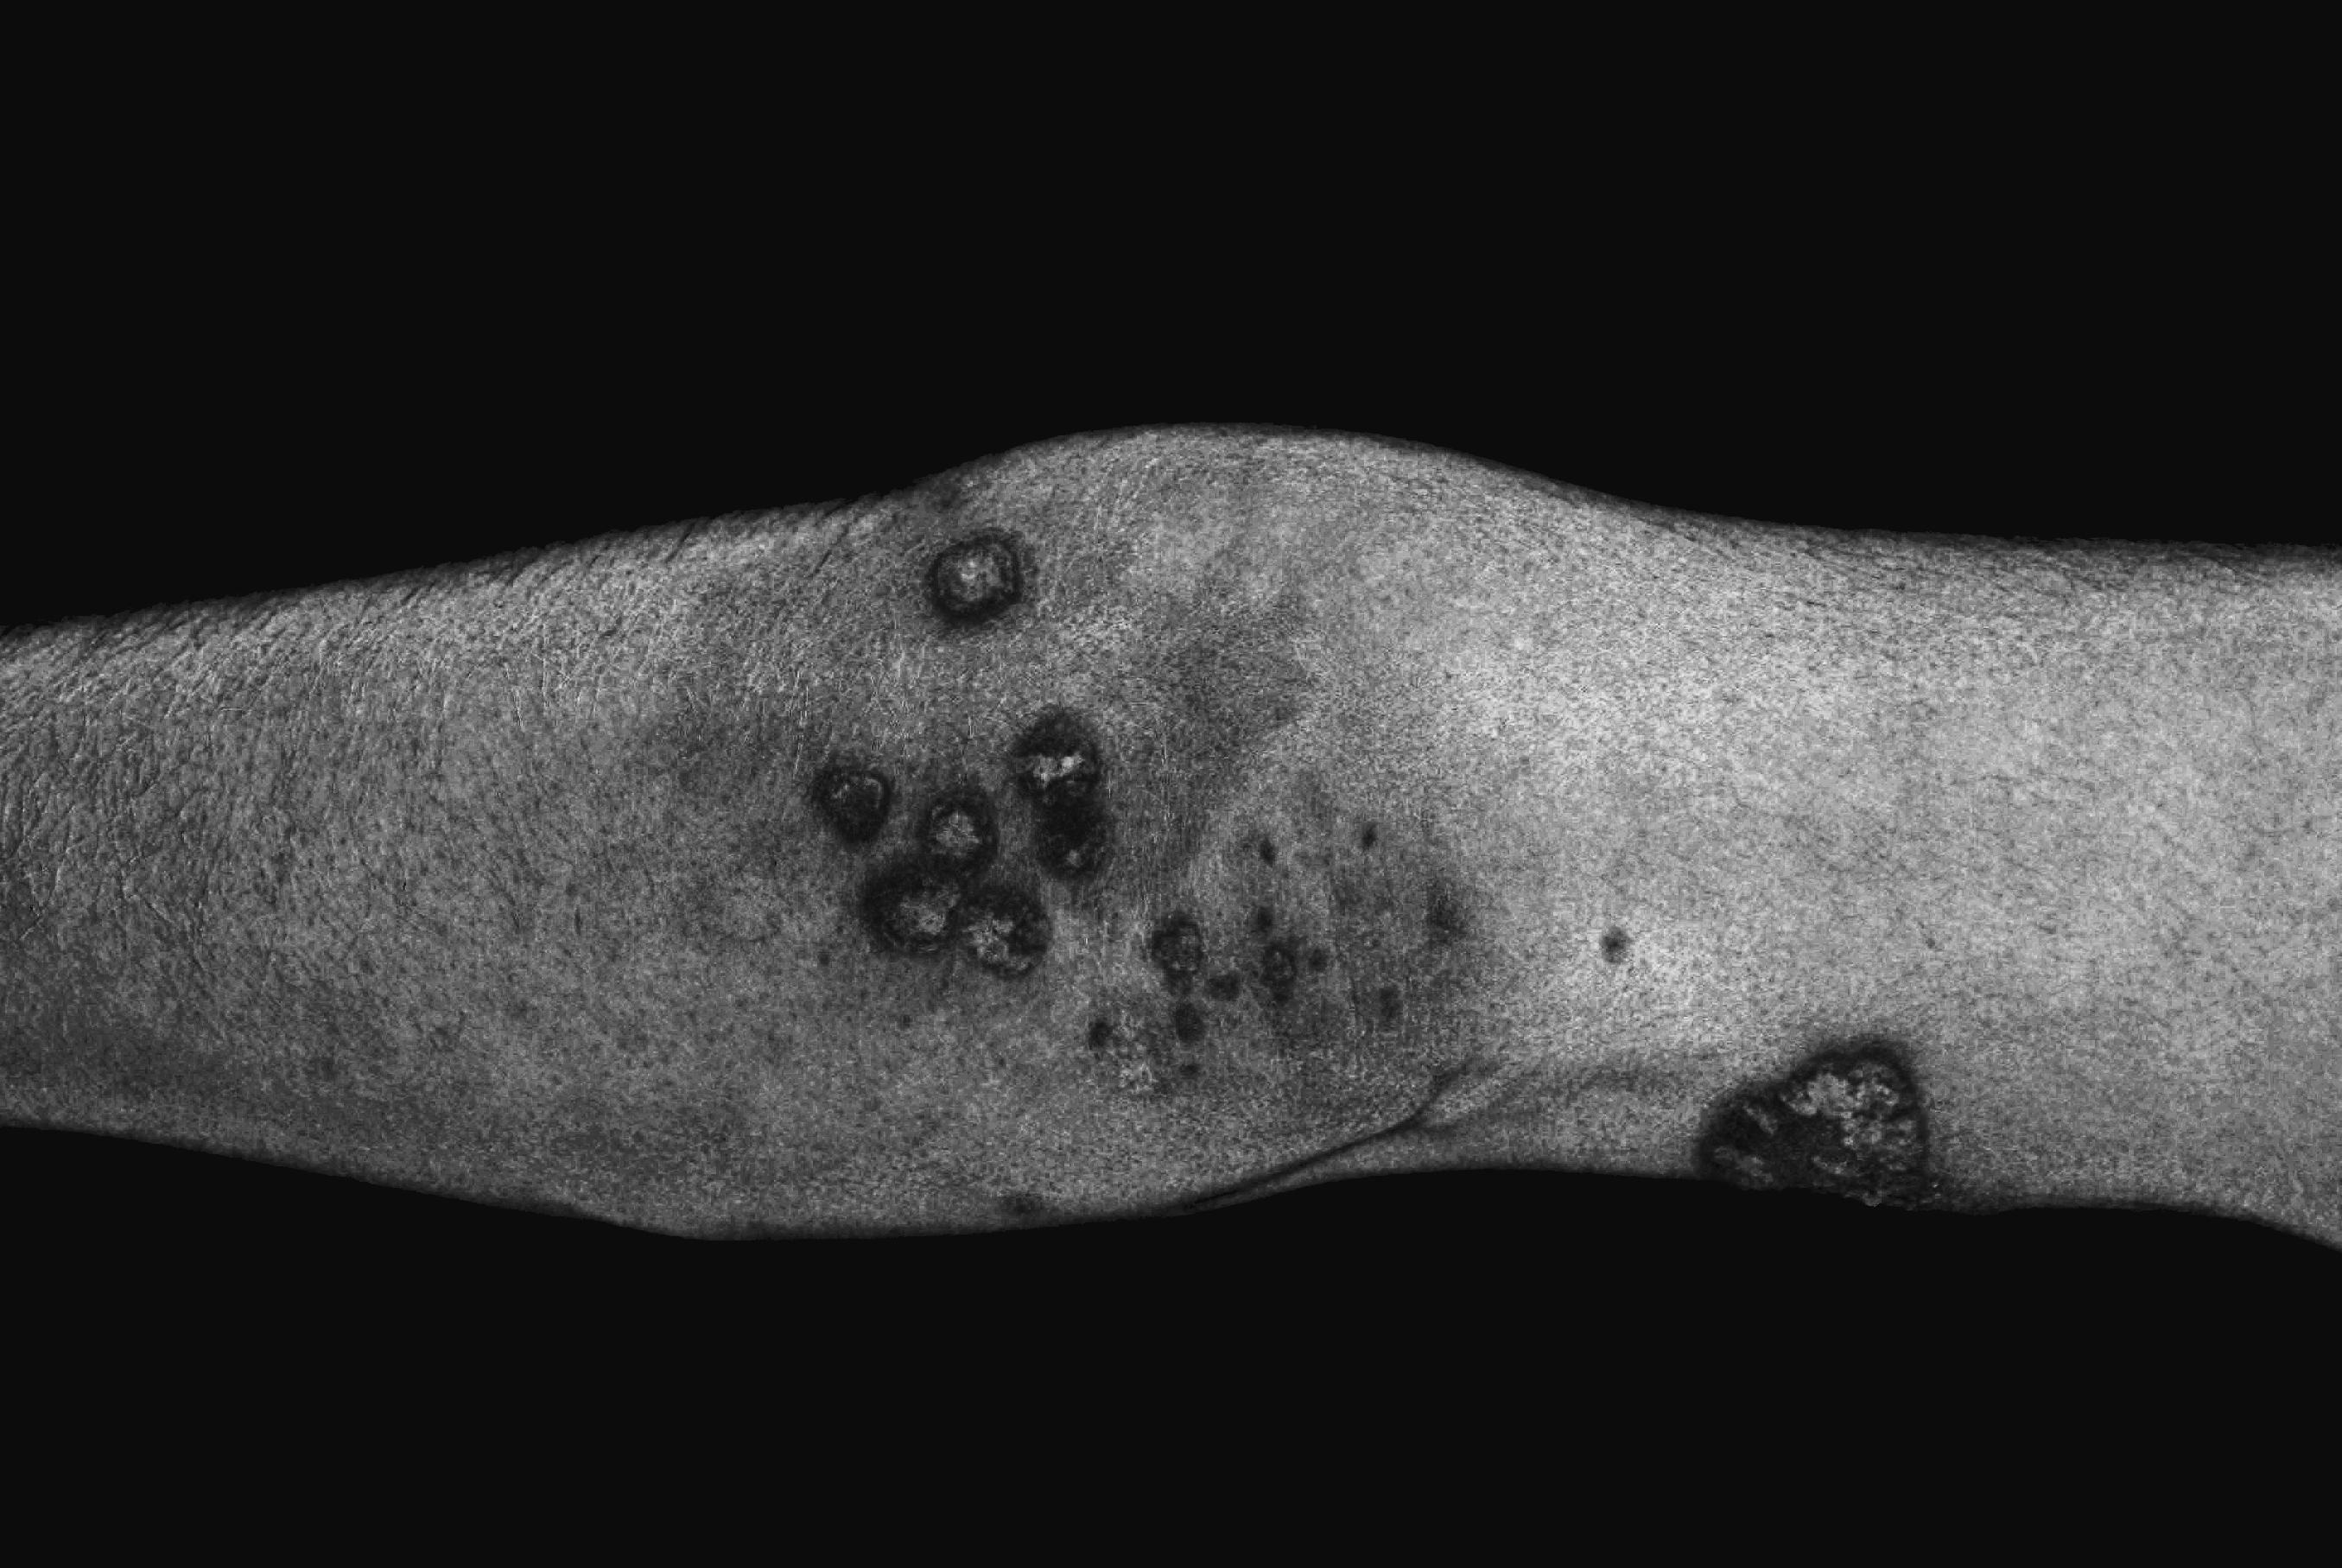

We are studying the possibilities of using the predominant color differences between normal and irritated skin regions as primary features to differentiate. Below are some preliminary examples of segmentation of various types of psoriasis manifestation using different color spaces.

Segmenting irritated regions in the B/G color space. Original image (left), processed color space (center), binary output (right) (without morphological postprocessing).

Segmenting the plaques (scales) in the Lab color space

Segmenting irritated red(dish) skin regions in the B-G color space with preprocessing, thresholding, and hole filling

Segmenting irritated red(dish) skin regions in the HSV (H) and YUV (V) color space separately, then thresholding and taking the intersection